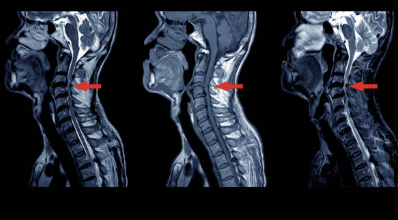

목 디스크는 경추 부위의 디스크 이상 중 하나로, 인접한 신경을 압박하여 다양한 증상을 유발할 수 있습니다. 다음은 목 디스크의 주요 증상 5가지에 대한 상세한 설명입니다.

- 저림 현상: 목 디스크로 인해 인접한 신경이 압박되면, 손가락이나 팔, 어깨 등에서 저림 현상이 나타날 수 있습니다. 이러한 증상은 다양한 정도로 나타날 수 있으며, 가끔은 동통과 함께 나타날 수도 있습니다.

- 무력감: 목 디스크로 인해 신경이 압박되면, 근육을 움직이는 데 필요한 신경 신호가 올바르게 전달되지 않아 근력이 감소될 수 있습니다. 이러한 무력감은 손, 팔, 어깨 등 다양한 부위에서 나타날 수 있습니다.